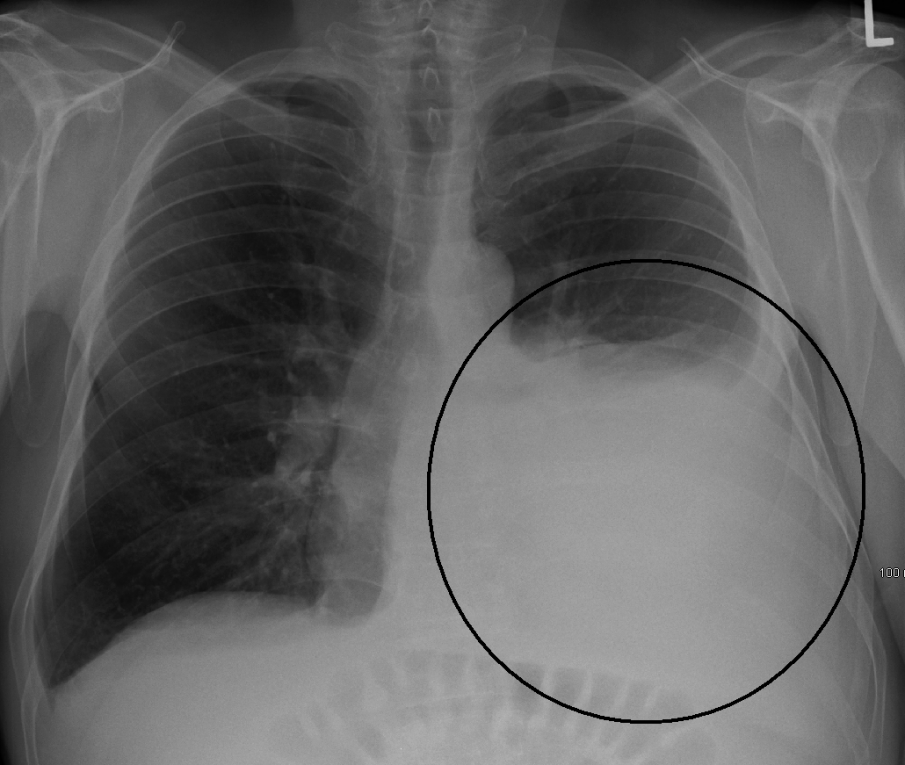

В Белодробната болница прегледите ще бъдат извършвани от пневмолози, тъй като в нередки случаи коронавирусната инфекция засяга предимно белите дробове, като при необходимост те ще пренасочват пациента за допълнителни прегледи при кардиолог, невролог или психиатър. Прегледът ще включва извършване на ЕКГ, изследване на дишането, пулсоксиметрия, а при необходимост и графия и кръвни изследвания.

Специалистите обясняват, че сред типичните симптоми на пост-Ковид синдрома са хронична отпадналост, проблеми със сърцето и с концентрацията, задух и кашлица, които се задържат месеци след активната фаза на болестта.